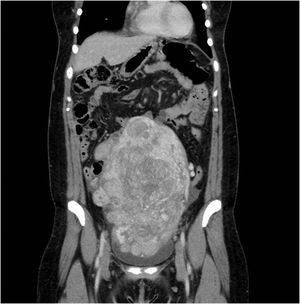

Clinical findingsGynecological ultrasound and Pelvic Magnetic Resonance revealed a huge tumor of about 15cm×10cm×17cm with a very clear boundary and highly vascularized consistent with myoma without malignancy signs. The study was completed with a Computed Tomography (CT) scan that confirmed the ultrasound and pelvic resonance findings. The mass generates an important collapse of the distal cava vein. Pelvic ovarian and hypogastric arteries seem to be dilated. No distant malignant masses are found.

The patient remained asymptomatic but a follow-up MRI, 2 months later, showed a polylobulated 84mm×48mm×35mm mass extending inside the right internal and common iliac veins. The tumor was isointense on T1-weighted imaging, with no restricted-diffusion pattern. Under the diagnosis of early relapse or progression of a previously missed intravascular leiomyoma the patient underwent a third laparotomic procedure with the removal of the right pelvic mass altogheter with the involved veins. Under heparin anticoagulation, the procedure involved the isolation of the mass with a careful dissection and ligation of the terminal branches of the right internal iliac vein, and the external iliac vein for the in-block resection of the tumor. The right common iliac vein was skletonized and proximally clamped to allow a safe removal by expression of the remaining tumor remaining in their lumen.

Ultrasound is the imaging technique more used to evaluate uterine masses, but it will not help to detect IVL at initial stages. In patients with cardiac involvement the echocardiography is the most sensitive technique. Computed Tomography, Arterial Computed Tomography, Magnetic Resonance are useful to evaluate the spread of the IVL and better plan the surgery (Figs. 1–3).